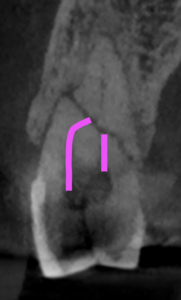

歯根の中央で水平に破断している。

ここで重要なことは破折片の口蓋側寄りの歯根には病変がないということだ。

そこは根管治療が不要である。

治療のゴールとしては、

このような形状に落ち着くのがベストであると言えるだろう。

もしその上部の根尖部に何かが起これば?

それはそこだけ抜歯であろう。

以前(USC時代の2015.3)にもそうしたケースがあったことを思い出す。

この時も根尖部は除去しなかった。

これが理想的なゴールである。